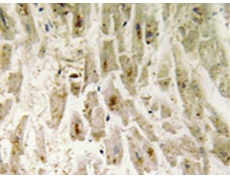

IHC positive control:

Human breast carcinoma tissue

IHC Recommend dilution:

50-100